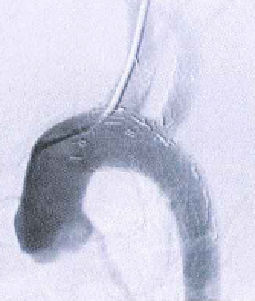

术后实时造影

6个月随访

A、D、G为整体图,其中A为分支支架、D为主支架和分支支架衔接处、G为主支架,B、C、E、F、H、I分别为A、D、G方框处的局部放大图